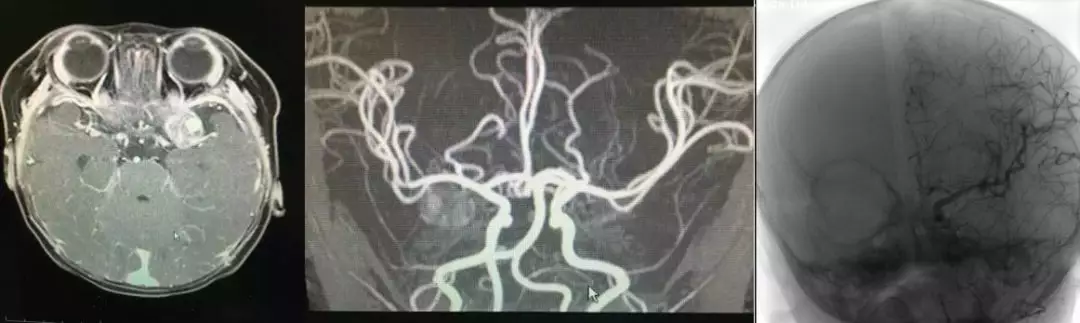

患儿邓某某,女,1个月,因“呕吐1周”入院。患儿1周前无明显诱因出现呕吐,非喷射性,进食后明显,呕吐物为胃内容物,无咖啡色样液体及胆汁。于消化内科就诊,予内科保守治疗呕吐症状缓解不明显,进一步行头部CT检查提示:双侧脑室内少量出血、幕上梗阻性脑积水(轻度);右枕区和左枕顶区硬膜下血肿;蛛网膜下腔出血。为求进一步诊治,入住湖南省儿童医院神经外科。

入院后进一步行头颅MRI平扫+增强示:左侧额叶类圆形异常信号影,呈明显均匀强化,考虑动脉瘤或血管畸形可能性大;蛛网膜下腔出血,颅后窝及左侧颞顶硬膜下血肿;双侧侧脑室扩张,第三脑室较饱满。进一步在全麻下行股脑动脉DSA造影示:左侧大脑中动脉巨大动脉瘤。

术前诊断:1.左侧大脑中动脉巨大动脉瘤 2.蛛网膜下腔出血 3.硬膜下血肿

虽婴幼儿血管细小,行股脑DSA术穿刺困难,但DSA检查对婴幼儿脑血管病的诊断和治疗极其重要,建议尽可能开展。我们的经验是在术中超声辅助下进行股动脉穿刺置管,选择4F导管进行全脑血管造影,可大大提高穿刺成功率。